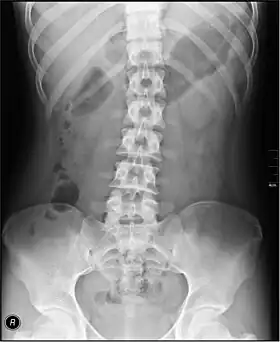

| Organs of the gastrointestinal tract | |